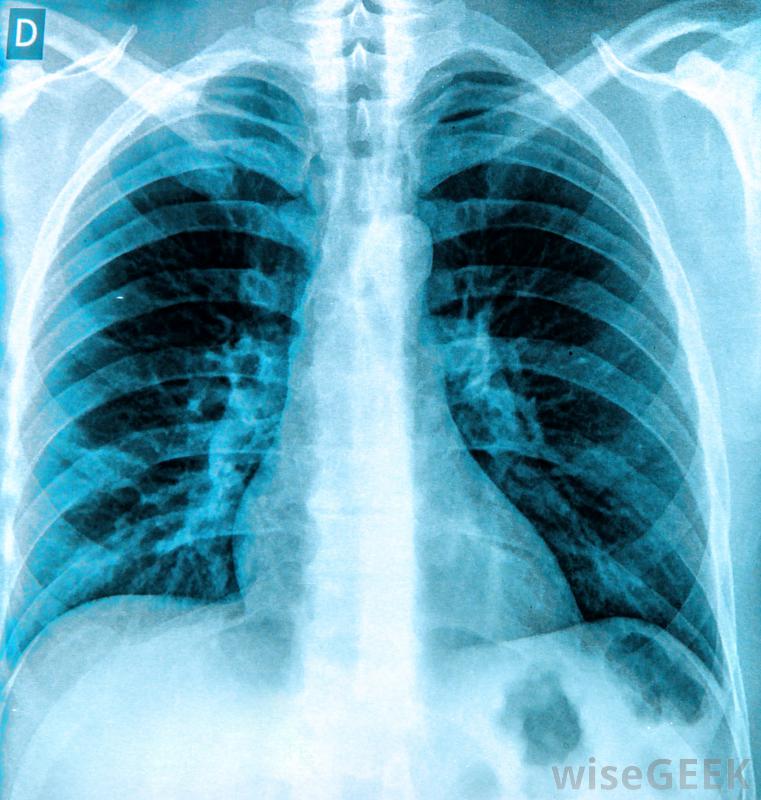

胸膜穿刺是從肺襯里和胸壁之間的空隙中取出液體樣本的過程。肺襯里是一層雙層膜,被稱為胸膜膜,包圍并支撐著器官。胸膜穿刺是作為診斷過程的一部分或作為移除的治療從肺部流出的液體。這個過程也稱為胸腔積液抽吸、胸腔穿刺或胸腔穿刺術。可以通過X光片來診斷胸腔積液在健康的肺中,胸膜膜層之間很少有液體。過剩的液體通常是由創傷或某種疾病引起的,如癌癥、感染或心力衰竭。在這種情況下,胸膜穿刺是一種診斷方法,抽取液體樣本并檢測是否存在細菌,病毒或其他提示液體積聚原因的線索。胸膜穿刺手術的常見風險包括在手術過程中或之后咳嗽或暈倒這種方法也可以用于治療某些疾病的癥狀。例如,一種叫做胸膜間皮瘤的癌癥會導致胸膜間積液,這種積水稱為胸膜滲出,引起不適,呼吸困難胸膜穿刺術是一種治療方法,可以清除液體,幫助患者呼吸更輕松。在健康的肺中,胸膜膜層之間幾乎沒有液體為了準備手術,病人通常會坐在椅子上或床沿上,病人必須靠在桌子上休息,胸部和頭部放在桌面上。病人的背部經過清洗和消毒,以防止感染,然后在穿刺部位注入局部麻醉劑。胸膜穿刺是一種從肺襯里和胸壁之間的空隙中取出液體的手術在胸腔積液穿刺過程中,將一根細長的針穿過皮膚插入胸膜膜之間的空隙,將液體樣本吸入針頭中。當針頭就位時,患者不要移動、咳嗽或深呼吸,以防止可能導致肺損傷的突然運動。如果測試是作為診斷過程的一部分進行的,則液體樣本將在實驗室中進行測試,以確定惡性細胞、微生物和蛋白質,從而提供診斷線索胸膜穿刺手術有幾個風險。最常見的風險是在手術過程中或之后咳嗽或暈倒。不常見的風險包括肺部疼痛、肺部塌陷和肺部積液。非常罕見的風險包括附近器官(如脾臟或肝臟)受損和胸腔出血空腔。一般來說,接受這種手術的人會在術后立即進行胸部X光檢查,以確保肺部不會被針頭損壞。胸膜穿刺后可立即進行胸部X光檢查以確保肺部沒有受損。